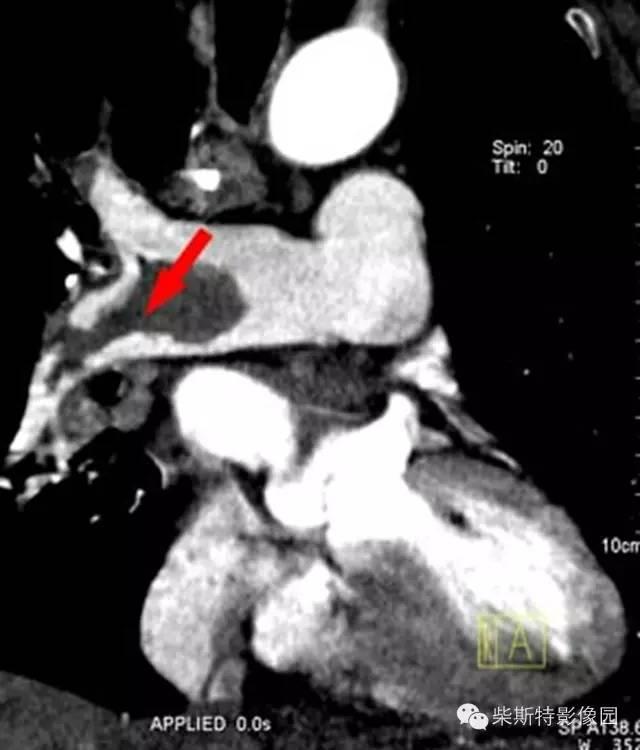

第一大名捕:肺动脉造影

红色箭头所指处即为栓子导致的充盈缺损。尽管肺动脉造影目前已经被肺动脉CTA所替代,但是其“老大”的地位还是无法撼动!

“老大”的绝招是其不仅可以提供整体的肺血管的解剖学资料,而且可以提供血流动力学参数,即可以用于诊断也可以用于治疗,如急性肺栓塞的导管内局部溶栓、捣栓、碎栓、抽栓,先天性肺动脉狭窄的球囊扩张、支架植入、肺动静脉瘘的栓塞治疗等。